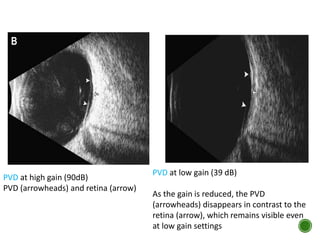

PVD at high gain (90dB)

PVD (arrowheads) and retina (arrow)

PVD at low gain (39 dB)

As the gain is reduced, the PVD

(arrowheads) disappears in contrast to the

retina (arrow), which remains visible even

at low gain settings